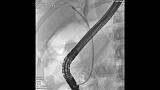

Здравствуйте. Пациентка, 32 года. Поступила на хирургическое отделение с диагнозом ЖКБ: холедохолитиаз. По данным МРТ: ЖКБ, множественные мелкие конкременты холедоха. При дуоденоскопии выявлено наличие вклиненного конкремента большого дуоденального сосочка. Выполнена прекатсфинктеротомия, получено 3 конкремента, диаметром около 0.4-0.5 см. Далее канюляция холедоха проволочным папиллотомом, выявлены многочисленные конкременты холедоха. Выполнена литоэкстракция ревизионным баллоном (на последнем фото окклюзионная холангиография - в просвете холедоха не конкременты, а пузырьки воздуха)).